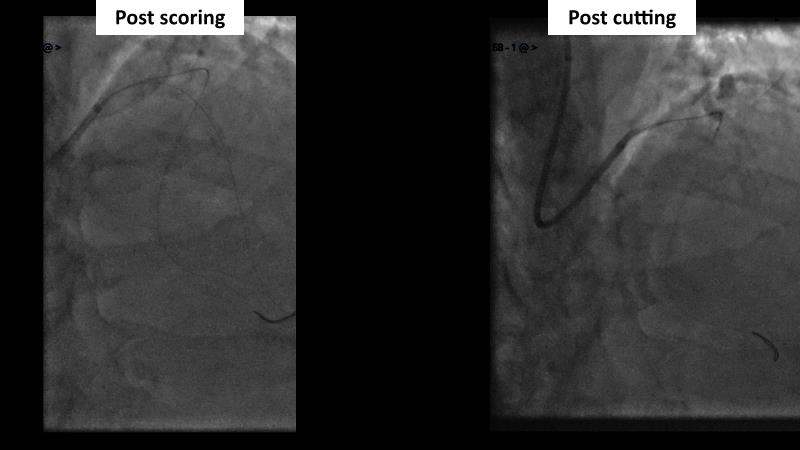

Sirolimus-coated balloon: expanding the scope of indications for complex coronary artery disease treatment

Watch this session to gain case-based insights on using DCBs in complex settings. Learn valuable tips and tricks for optimal DCB application, including the best timing and situations for their use. Discover how to effectively implement a hybrid strategy that combines DES and DCB when needed.

- To learn about tips and tricks on how and when to use a DCB: the ideal time and situation of DCB application in various complexities

- To utilise the hybrid strategy approach Combining DES and DCB when the situation demands